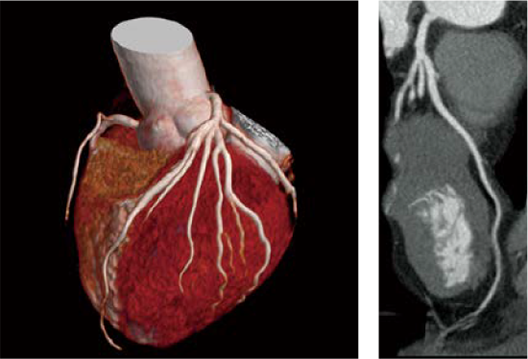

This function automatically selects the cardiac phase with the least heart motion after cardiac CT imaging. The amount of motion in each cardiac phase was calculated*5 based on the collected data and ECG information, and the cardiac phase with the least motion was selected as the appropriate reconstruction condition. CardioHarmony reduces the time required for finding the appropriate cardiac phase and image reconstruction necessary after cardiac CT imaging.

Reconstructed cardiac phase 75%

120kV、0.35sec/rot、Beam Pitch 0.1719、Intelli IP Lv3